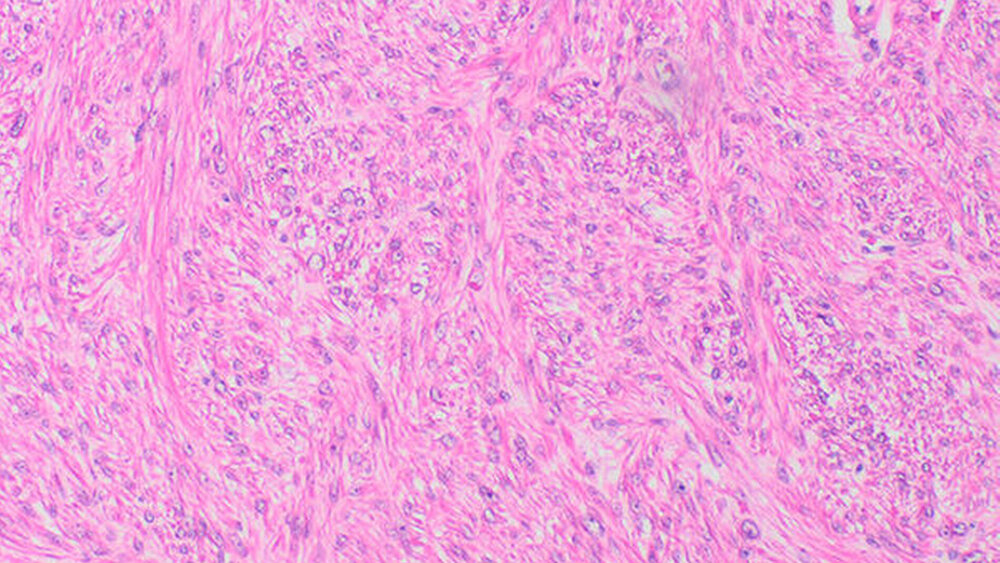

Zur Kontrolle erfolgten MRT-Kontrollaufnahmen des ganzen Körpers in einem dreimonatigen Abstand. Bei Vorstellung in unserer Klinik zeigte sich abgesehen von einem diskreten Bulbushochstand und Exophthalmus rechts ein unauffälliger klinischer Befund. Im MRT zeigte sich eine intraorbitale Raumforderung (Abbildung 1). Die histologische Untersuchung bestätigte den Verdacht auf eine Neumanifestation des Leiomyosarkoms (Abbildungen 2, 3).